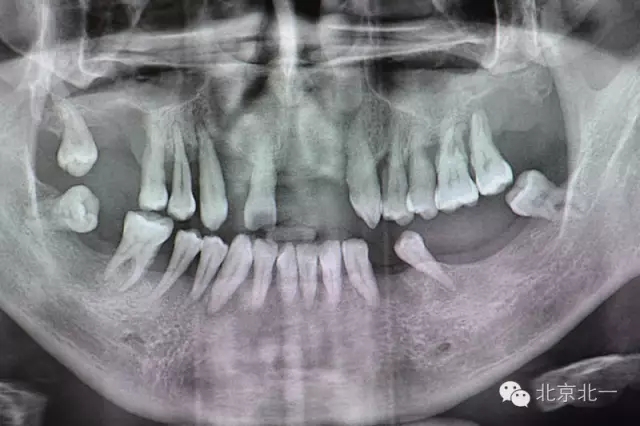

圖二:術(shù)前全景片